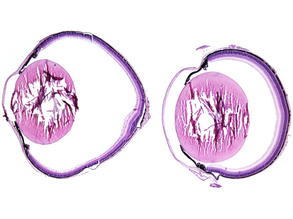

Retinal Rhythms